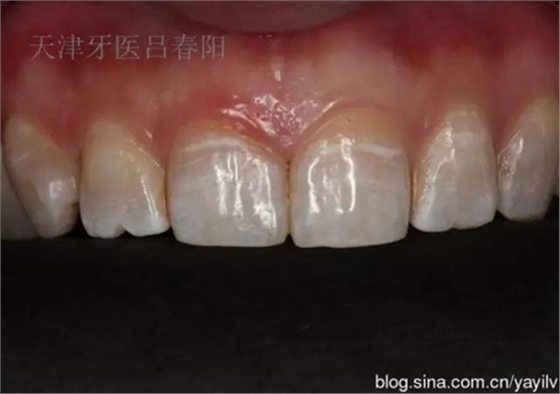

發(fā)一個最近完成的病例吧,雖然齲洞不大,但是挺好玩的,我自己認為。